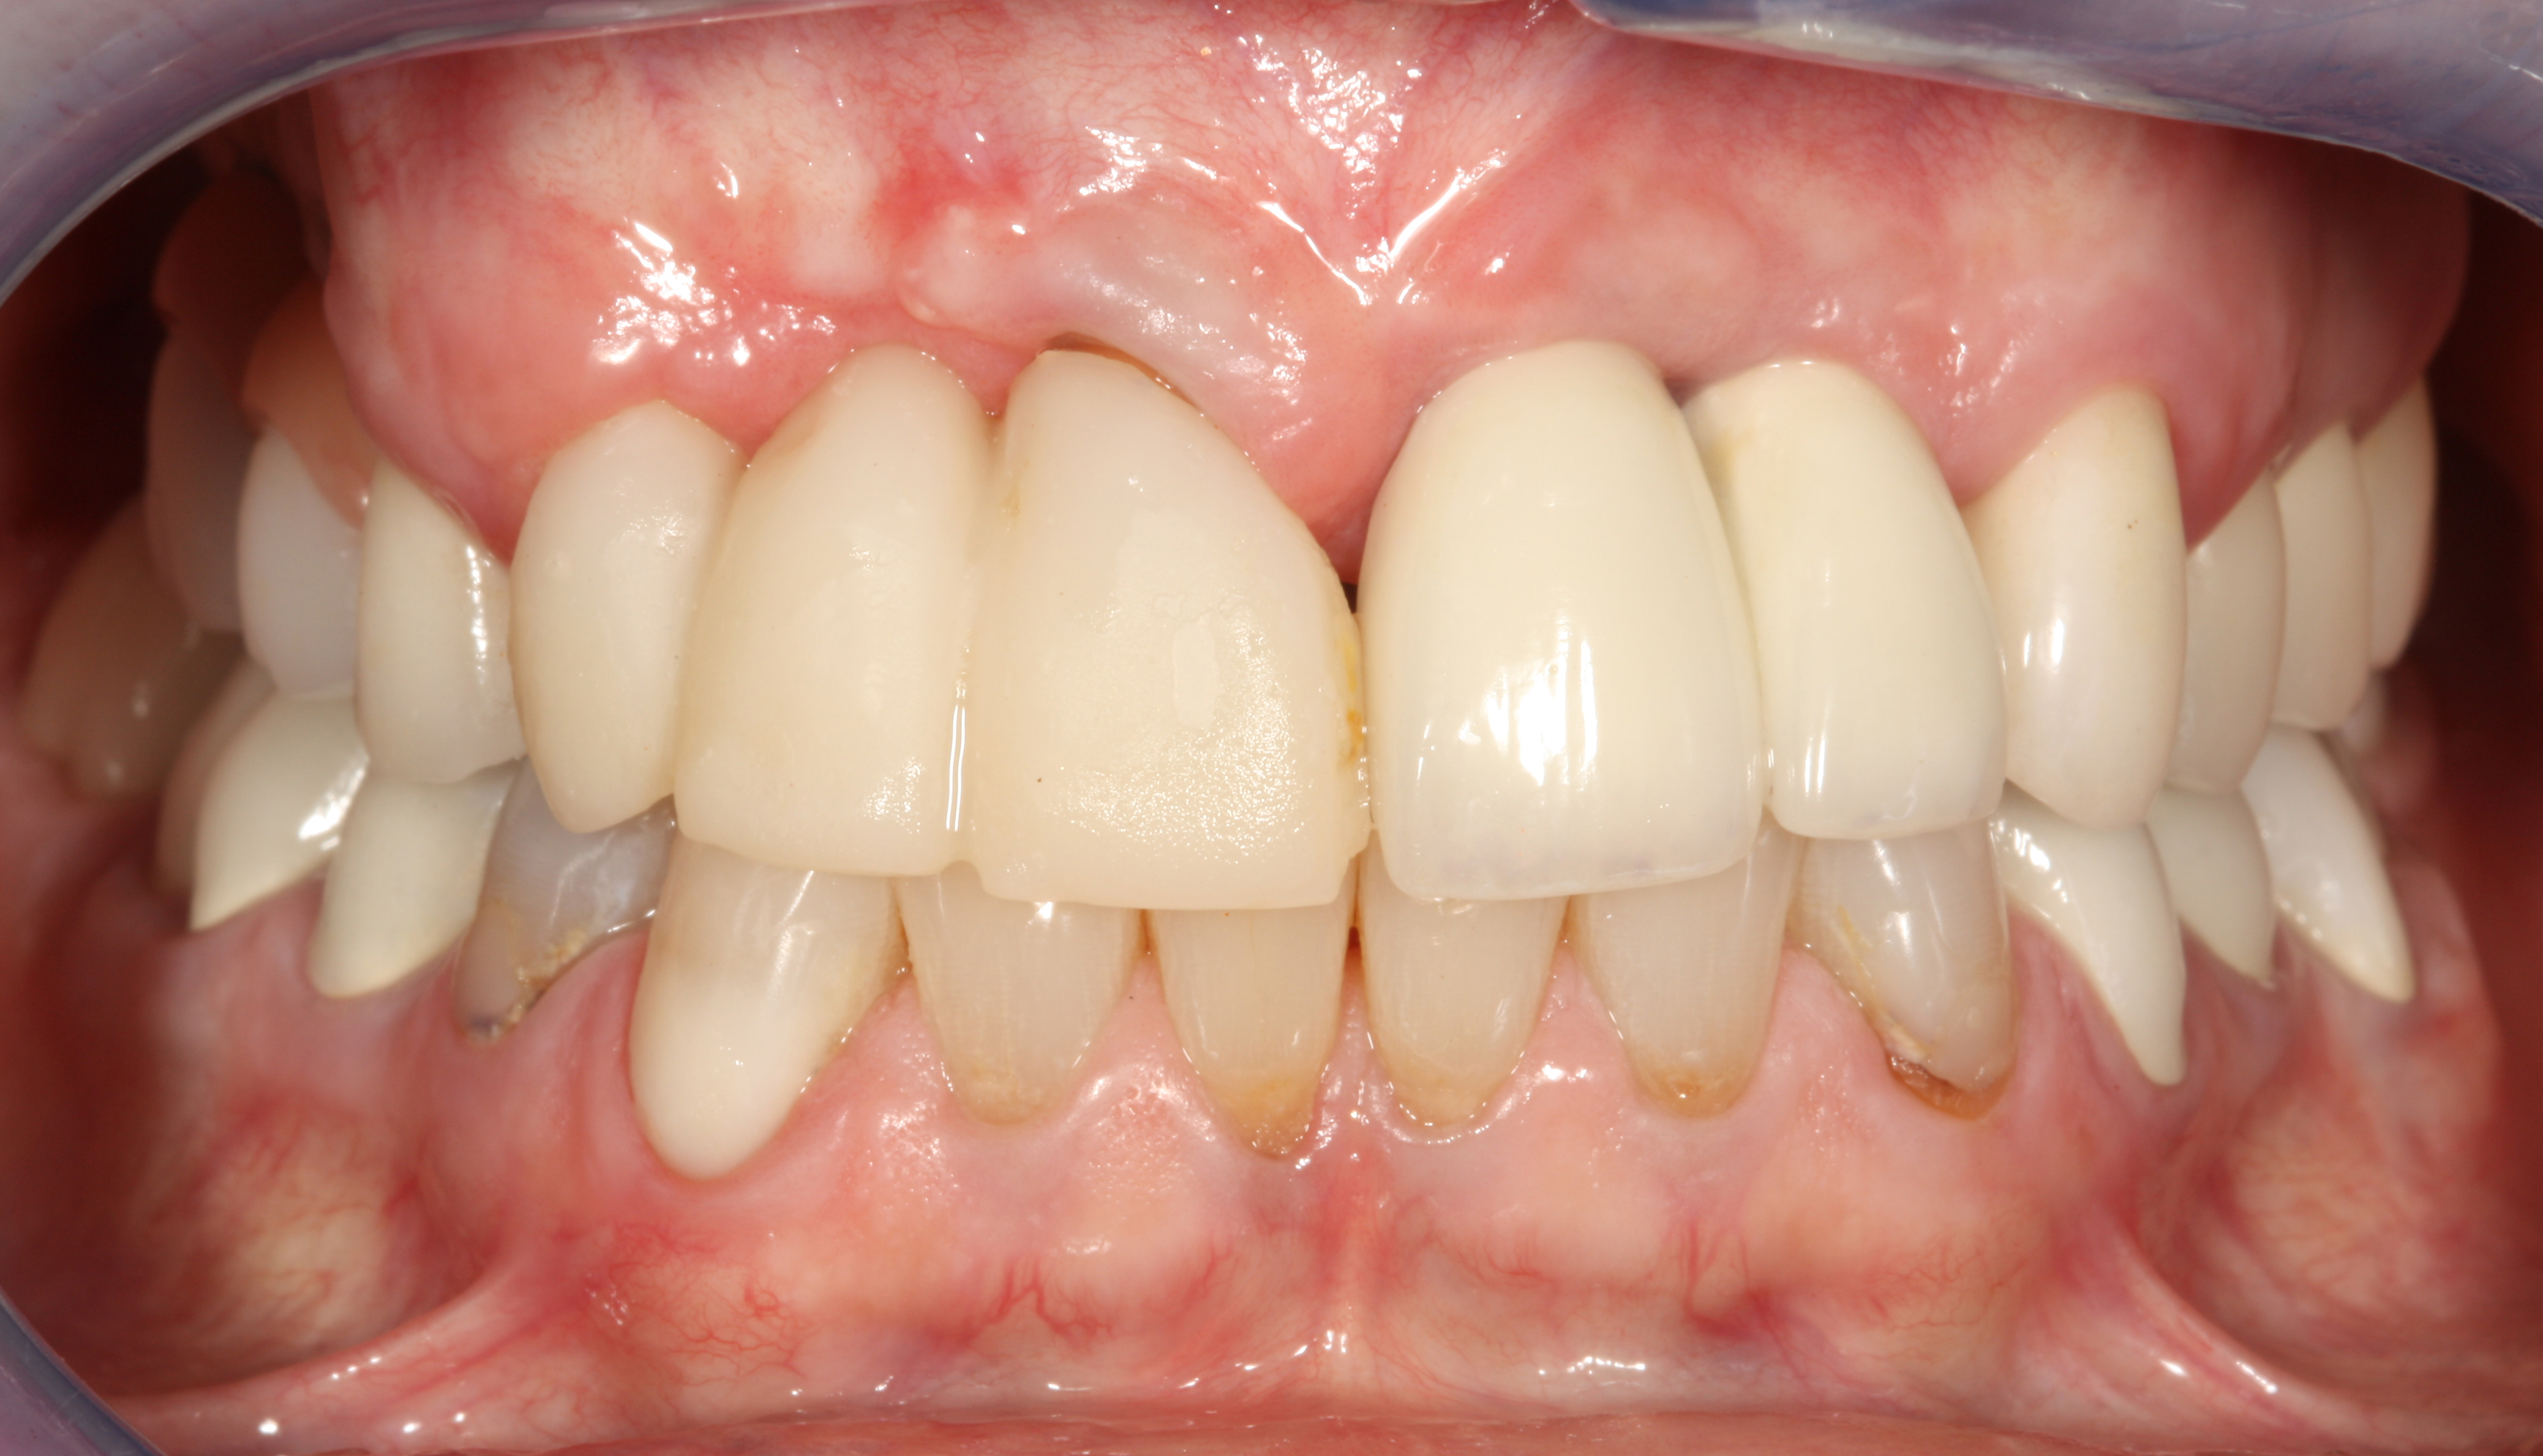

Problem: The implant is placed too facially, and there is significant labial gingival recession, contour change, and mucosal discoloration around the implant, abutment, and crown (Figure 3 and Figure 4). The implant attachment apparatus is intact and healthy, but the patient has a thin periodontal phenotype.

The following case report provides an example of this case scenario: A 28-year-old white female patient presented with her maxillary right lateral incisor significantly longer than the contralateral tooth following restoration of an existing crown that was 10 years old (Figure 3). The patient was dissatisfied with the esthetic appearance of the restoration due to the increased length, recession of the gingival tissues, and discoloration of the surrounding mucosa (Figure 4). Similar to case scenario No. 1, the first step in treatment was to decoronate the healthy implant by placing a flat surgical cover screw and employing a provisional resin-bonded-retained (RBR) prosthesis as a transitional fixed restoration (Figure 5 and Figure 6). The gingival augmentation in situ was allowed to take place for 2 to 3 weeks and was evaluated after that time (Figure 7).

Fig 3. A patient presented with a high smile line and midfacial recession of the maxillary right lateral incisor as evidenced by the increased tooth length compared with the contralateral lateral incisor.

Fig 4. Intraoral view of tooth No. 7 with the gingival zenith more apical than the adjacent central incisor and canine tooth.